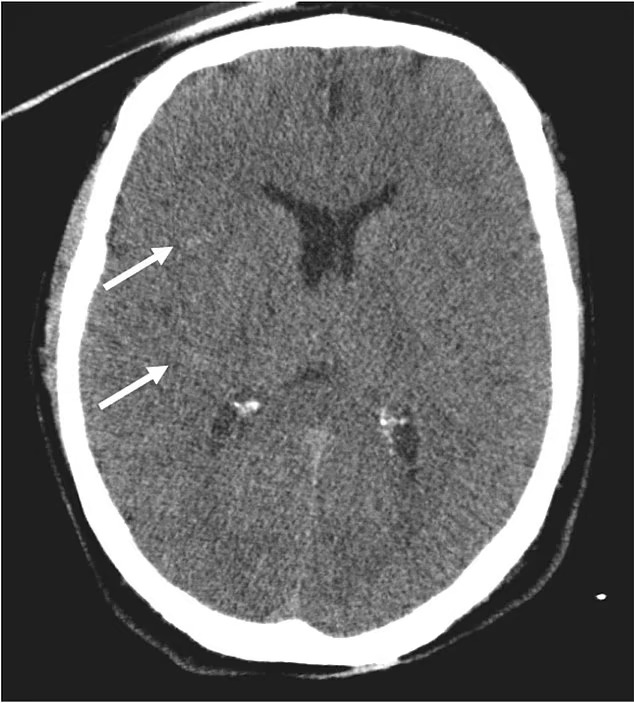

وأصيب الإيطالي بحروق في جلده وشعره ومناطق متفرقة من جسده، وهو ما يعتقد المسعفون أنه نجم عن انزلاقه على إطار الدراجة البيضاء الساخنة عندما أصيب، حيث أكدت الصحيفة أنه انفجرت لديه طبلة أذنه وكشفت الأشعة المقطعية عن نزيف في دماغه.

وأجرى الأطباء عملية جراحية للرجل الإيطالي بوقف النزيف قبل أن يتوجه إلى العناية المركزة، وبعد الجراحة تم تخديره وخضع لمزيد من الفحوصات.

ساء وضع الرجل بشكل ملحوظ مع تقدم الأيام، وبينت الأشعة المقطعية وجود تلف في الدماغ، وتوفي في اليوم العاشر بعد دخوله المستشفى بسبب انخفاض تدفق الدم إلى أعضائه بسبب السكتة القلبية والنزيف.